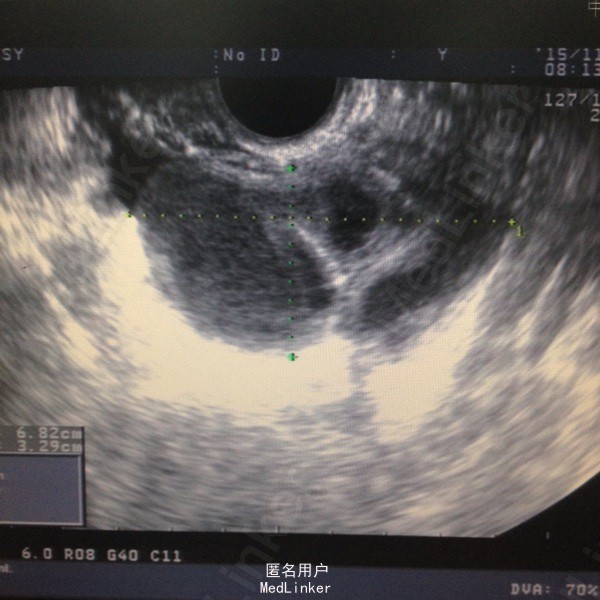

40岁女性,G2P2,皆为顺产。因下腹痛、发热伴阴道分泌物增多3天入院。发热最高达38.5摄氏度,伴头痛、肛门坠胀感,急诊查血常规:白细胞13.53*10E9/L,CRP 77.8mg/l,B超提示双侧附件囊性包块,大小分别为72*32mm,及42*36mm。

此病人已达到盆腔炎的诊断标准,入院予对症支持处理,考虑患者盆腔包块较大,较局限,予B超引导下穿刺置管引流。